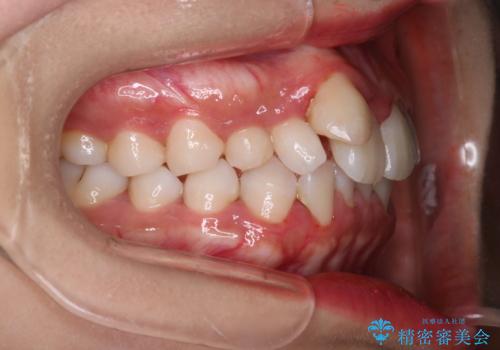

【インビザライン】八重歯が気になる

- 乳歯を抜歯してスペースを確保し八重歯の改善を行いました。

インビザラインをしっかり使用していただいたので、きれいな歯並びになりました。